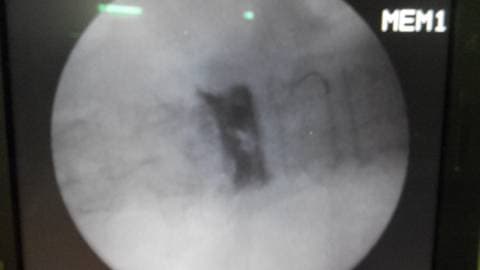

Баллоны в теле позвонка в раскрытом состоянии в боковой проекции

Боковая проекция показывает размещение и раскрытие баллонов в теле позвонка